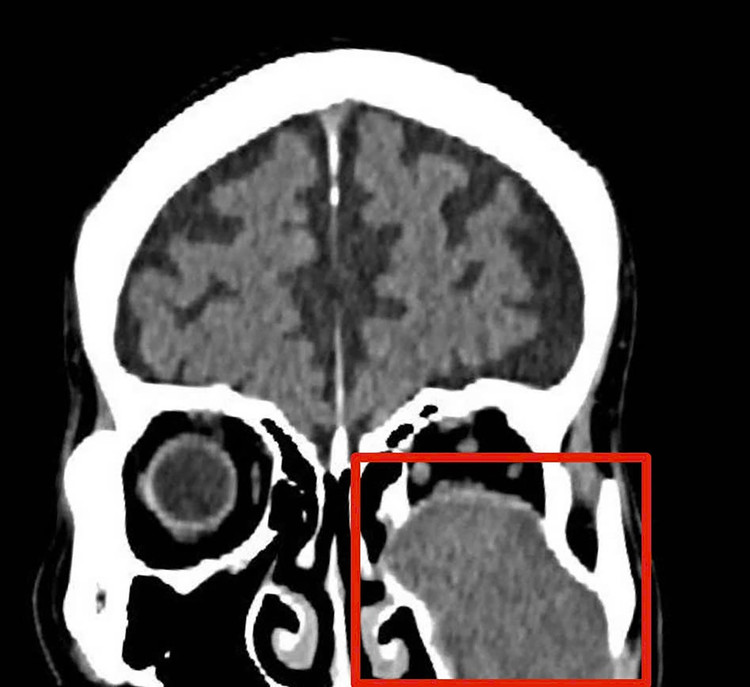

Hình ảnh chụp phim cho thấy khối u ăn mòn tiêu xương sàn ổ mắt. Ảnh nguồn tienphong.vn

Kết quả chụp chiếu và hội chẩn liên khoa xác định, khối u nhầy xoang hàm trái của bệnh nhân có kích thước lớn, đã ăn mòn tiêu xương các thành xoang hàm, đồng thời xâm lấn và làm tiêu xương sàn ổ mắt.